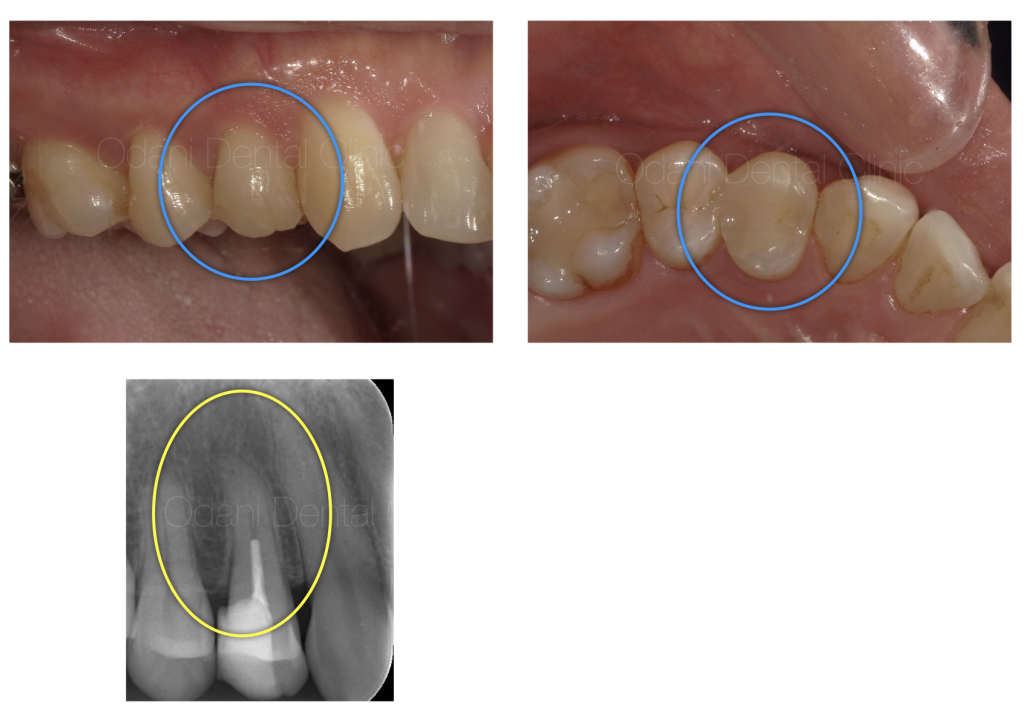

診察および画像検査の結果、根管内に細菌が残存しており、それに伴う炎症反応によって症状が出ていると考えられました。

CT画像では、歯の根の周囲の骨が少し吸収していることが確認でき、このまま放置すると、さらに感染が進行し、骨の吸収が拡大する可能性が高いと考えられました。

根管治療後、 術後3ヶ月の状態です。黒い影がなくなり、骨が回復している様子が伺えます。

痛みの症状もなくなったため、最終のかぶせ物の治療を行いました。